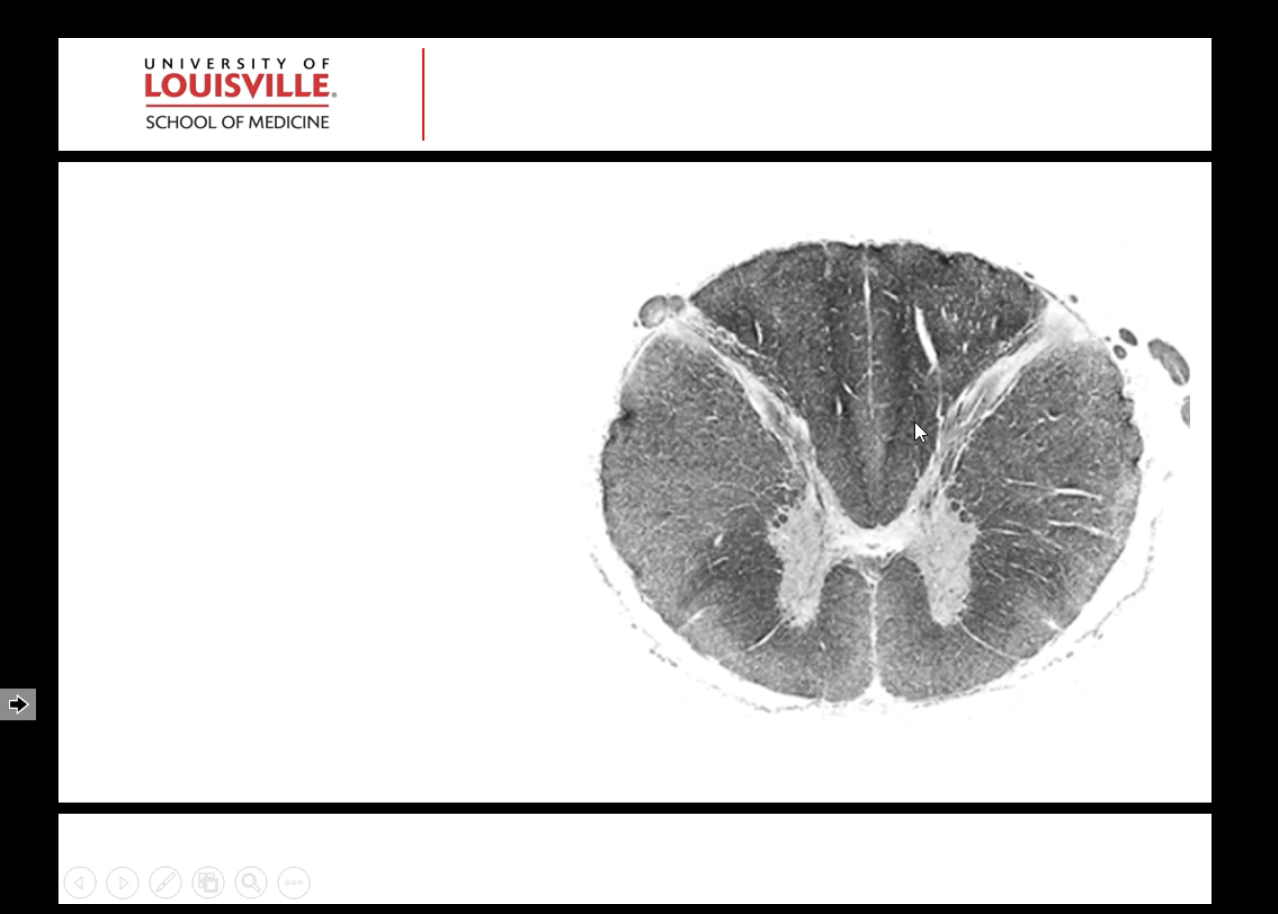

What spinal level is this?

What are some of its characteristics?

Thoracic